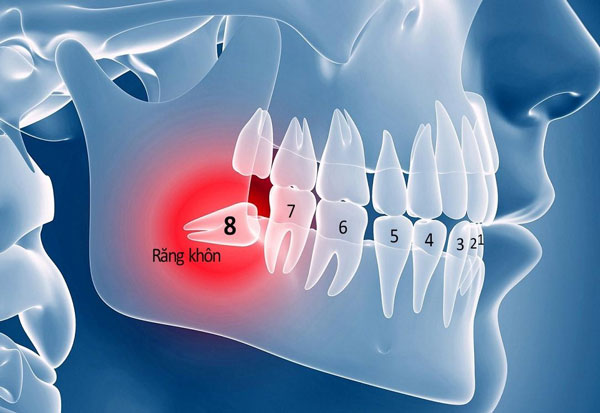

Hàm răng của một người trưởng thành sẽ có 32 chiếc răng, bao gồm: 8 răng cửa, 4 răng nanh, 8 răng hàm trước, 8 răng hàm sau và 4 răng khôn. Trong đó, răng khôn hay còn gọi là răng số 8, mọc sau cùng, nằm sát vách hàm và nằm cạnh răng số 7. Thực tế, răng khôn không có chức năng ăn nhai hay chức năng thẩm mỹ.

Răng khôn mọc ở độ tuổi trưởng thành từ 17 – 25 tuổi, lúc này bề mặt nướu dày hơn, xương hàm đã phát triển ổn định và cứng hơn trước. Đồng thời, răng số 8 có diện tích lớn cùng hình dáng khá phức tạp và một số trường hợp vòm miệng không đủ chỗ để chúng mọc bình thường, dẫn đến mọc lệch, chen chỗ các răng khác.

Chính vì vậy, khi răng khôn xuất hiện sẽ khiến mọi người cảm thấy đau nhức, nướu sưng hoặc đỏ, đau nhức, ăn uống khó khăn, hàm bị co cứng và không thể há to như bình thường, hơi thở có mùi, thậm chí bị sốt cao. Bên cạnh đó, nếu răng khôn mọc lệch hoặc mọc ngầm nhưng không can thiệp kịp thời, sẽ dễ tích đọng thức ăn gây sâu răng, viêm nướu, đâm thủng chân (thân) răng số 7 hoặc làm xô lệch cả những răng còn lại.